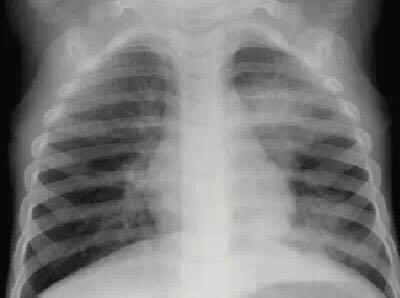

3、肺部啰音出现比较迟,所以容易误诊,但是肺部影像学改变大多数为实变影,吸收比较慢。